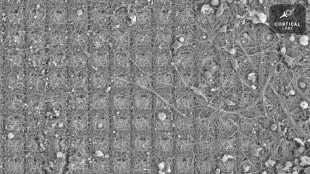

Des neurones doués de sensations ont appris à jouer à un jeu vidéo

Des neurones cultivés dans une boîte de Petri sont capables d'apprendre à jouer à Pong, le grand classique des jeux vidéo, faisant ainsi preuve d'un "comportement intelligent et doué de sensations", selon des chercheurs en neurosciences australiens.